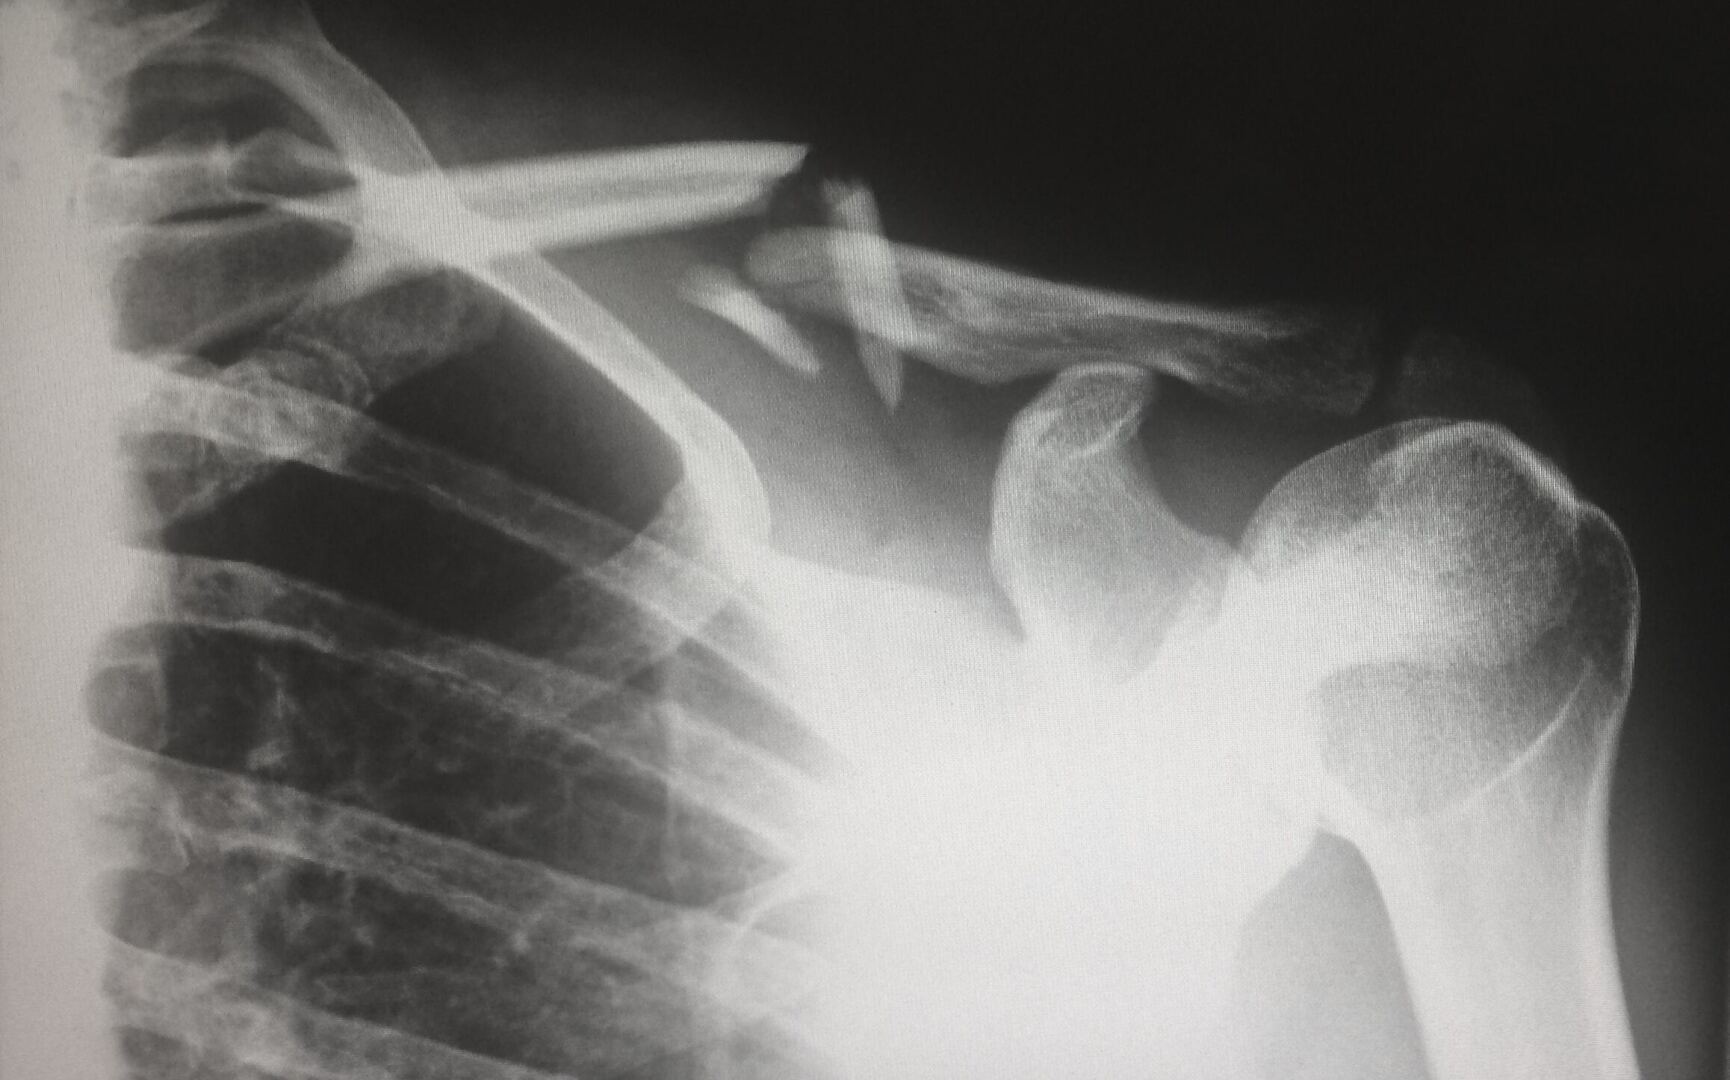

Примером такой травмы может быть комбинация переломов костей, повреждения внутренних органов и черепно-мозговая травма в результате автомобильной аварии.